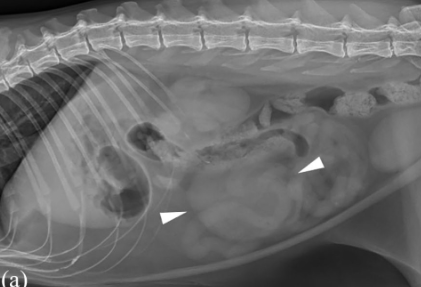

자료는 항암을 전제로 부분절제를 하여 삶의 질을 높이는것에 관한 실마리를 던져주는 논문이다.

썩 만족스러운 결과는 아니지만 보호자의 요청에 의해 종양의 부분절제를 무조건적으로 거부할게 아니라

고려해볼 수 있는 상태가 되는 근거 논문이니 참고하기 바람.